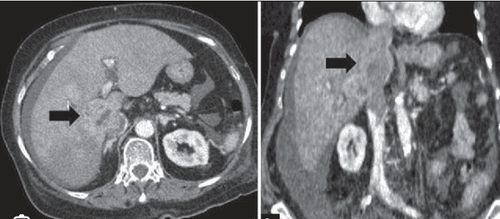

Về dữ liệu hình ảnh trước phẫu thuật, theo hai báo cáo ca bệnh bao gồm 92 bệnh nhân và 94 bệnh nhân, độ chính xác của siêu âm là 0%-33%, chụp cắt lớp vi tính (CT) là 15,7%-18,2% và chụp cộng hưởng từ (MRI) là 4,3%-22,7%. Điều này có thể là do sự thay đổi về tỷ lệ và phân bố của các thành phần mô khác nhau trên hình ảnh, cản trở việc chẩn đoán. Ví dụ, các đặc điểm hình ảnh nổi bật nhất của u tế bào biểu mô quanh mạch máu gan là mô mỡ trưởng thành và mạch máu thành dày ở trung tâm. Điều này làm cho u tế bào biểu mô quanh mạch máu gan được đặc trưng bởi mô mỡ dễ chẩn đoán.

Hình anh chụp cắt lớp của u tế bào biểu mô quanh mạch máu

Tuy nhiên, u tế bào biểu mô quanh mạch máu gan có tính thay đổi và cũng có thể biểu hiện dưới dạng khối u chứa mô ít mỡ hoặc mô không mỡ. Hơn nữa, sự hiện diện của chất béo được phát hiện là không đáng tin cậy vì một số hydrocarbon có chứa chất béo và những chất béo này cũng có thể bắt chước u tế bào biểu mô quanh mạch máu gan trong quá trình trình bày. Điều này sẽ ảnh hưởng tiêu cực đến các chuyên gia hình ảnh và dễ dẫn đến chẩn đoán không chính xác. Để giải quyết vấn đề này, nhiều chuyên gia lâm sàng đã áp dụng nhiều cách tiếp cận khác nhau. Ví dụ, Ding và cộng sự, thông qua việc kết hợp kiểm tra siêu âm, CT, MRI và chụp mạch ở 79 bệnh nhân, đã đạt được độ chính xác chẩn đoán là 52%. Wang và cộng sự đã sử dụng siêu âm B bổ sung và siêu âm tăng cường độ tương phản (CEUS) để phân biệt u tế bào biểu mô quanh mạch máu gan với các khối u gan lành tính khác.